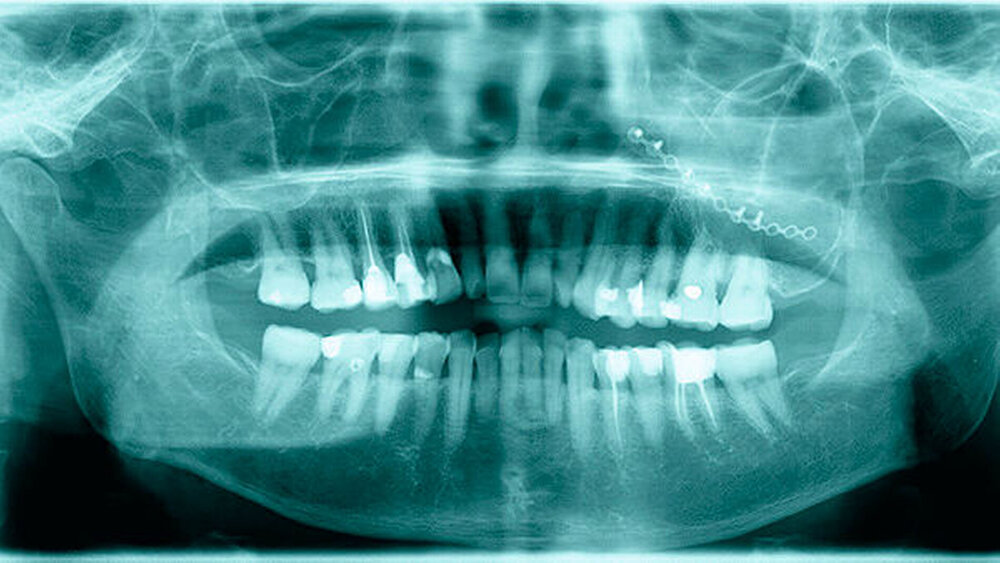

Intraoral zeigte sich bei guter Mundhygiene folgende Situation: Dem klinischen Befund schloss sich ein OPG (Orthopanthomogramm) als zusätzliche diagnostische Maßnahme an. Auf dem OPG sieht man eine ringförmige Struktur in der Kieferhöhle links mit einer zystischen Formation um die ringförmige Struktur (Abbildung 1).

Laut Eigenangaben hatte die Patientin in dem Bereich kein Trauma, keine Operation oder Infektion, allerdings zeigte sie deut- liche Symptome einer linksseitigen Sinusitis, vor allem beim Bücken. Zur weiteren Diagnostik wurde eine Computertomografie (CT) in der radiologischen Abteilung des Einsatzlazaretts durchgeführt (Abbildungen 2 und 3). Im CT zeigt sich ein malrotierter, verplumpter 28er. Zahnwurzeln lassen sich nicht abgrenzen. Um die Zahnkrone herum zeigt sich eine 3,9 cm x 2,4 cm x 3,5 cm große, zystische, rand- ständig verkalkte Formation. Diese füllt subtotal die linke Kieferhöhle aus. Der Zysteninhalt zeigt sich homogen ohne Septierungen. Die Dichte ist mit etwa 30 HE angehoben. Leicht expansives, jedoch kein infiltratives Wachstum. Kein Hinweis auf ein malignes Geschehen.